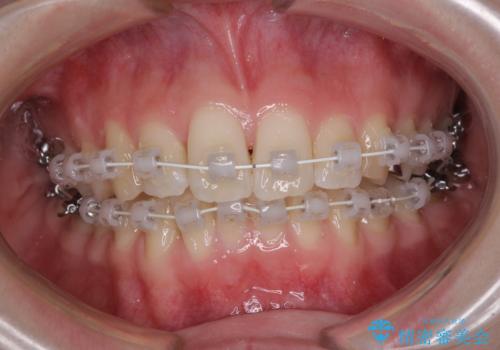

- 急速拡大装置・審美装置

急速拡大装置により上顎骨を側方に拡大し、ワイヤー装置により歯列を整えることとしました。

左右ともに奥歯の咬み合わせには大きな問題がなく、窮屈な歯列を解決すれば歯列を整えることできたため、僅か1年で終えることができました。